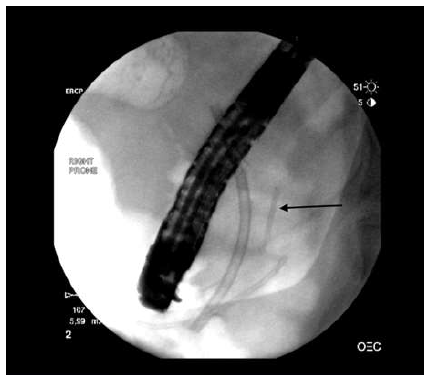

Figure 2: Broken Stent Neck of Pancreas

Figure 3: Stent Piece Neck of Pancreas